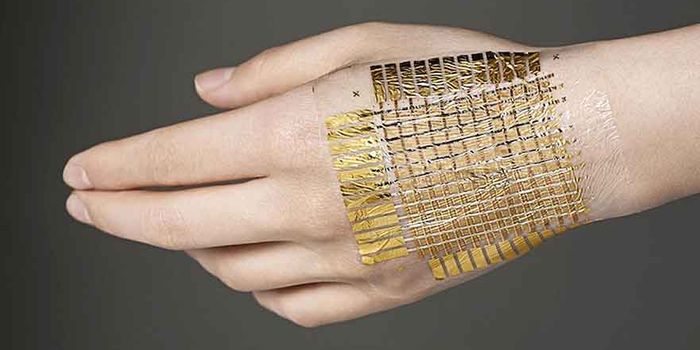

SEP 16, 2021Clinical & Molecular DXForget uncomfortable chest straps or clunky wristbands—thanks to a new innovation in nanotechnology, your t-shirt ...

OCT 21, 2021Clinical & Molecular DXA team of engineers has developed a wearable device that can monitor blood sugar levels minus the painful finger prick. ...

APR 01, 2021Clinical & Molecular DXWhat is e-skin technology? These wearable electronics are soft, flexible, and stick on to the surface of skin with a vas ...

APR 06, 2017Clinical & Molecular DXAt first glance, the sheet of electronic resembles a used candy wrapper rather than a sophisticated wearable device. But ...